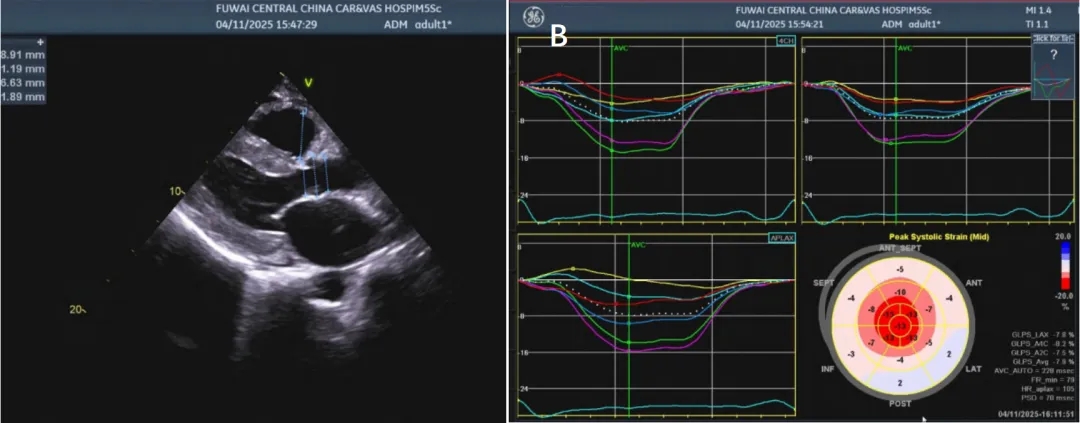

4.3超声心动图:CA超声心动图的典型表现为室壁增厚,双房扩大,左心室腔大小正常,心肌散在颗粒状强回声,但多在CA晚期出现。CA患者左室射血分数正常或轻度减低,左室射血分数减低者预后较差;心包积液常见,但大量心包积液较少出现。有研究者应用二维斑点追踪技术对80例AL型CA,92例ATTR型CA患者行超声心动图检查,发现AL型,ATTR型CA患者均表现为左心室整体纵向应变减低,但心尖应变保留(左心室基底段及中间段纵向应变减低,心尖段纵向应变无明显减低)。此外,应用二维斑点追踪技术还可对CA和肥厚型心肌病进行鉴别诊断。超声血流多普勒和组织多普勒可评估心室舒张功能,CA患者几乎均存在重度舒张功能不全,表现为二尖瓣血流减速时间缩短,左心室壁位移速度减低。部分ATTRwt型CA患者超声心动图可见主动脉瓣狭窄。应用三维斑点追踪技术可早期诊断CA。(见图4)

图4.心脏彩超。A. 胸骨旁长轴视图显示左心室增厚,左心室大小正常,心肌内有颗粒状强回声。左房增大,少量心包积液。B. 心脏淀粉样变患者二维斑点追踪显像纵向应变牛眼图示左心室基底段和中间段的纵向应变明显降低,而心尖部纵向应变正常,显示为深红色,呈“心尖保留”征象,又称“草莓征。